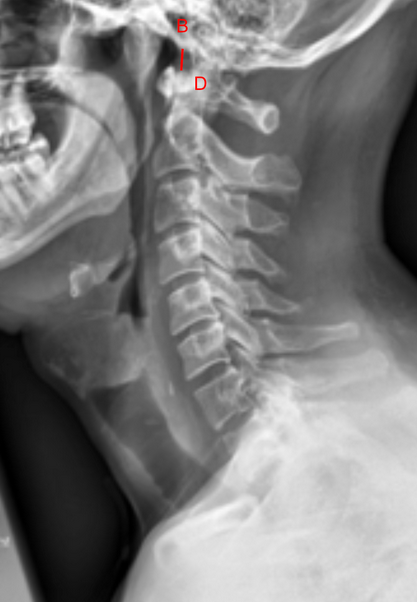

The Basion-Dens Interval (BDI) is a radiographic measurement used to assess atlanto-occipital alignment and integrity of the craniovertebral junction.

It measures the distance between the basion (anterior margin of the foramen magnum) and the tip (apex) of the odontoid process (dens).

• Obtain a neutral lateral cervical spine X-ray (as shown in the provided images).

• Basion (B): The anterior inferior margin of the foramen magnum (visible as the anterior skull base point).

• Tip of the Dens (D): The most superior point of the odontoid process (C2).

• Draw a straight line from the basion (B) to the tip of the dens (D).

• Measure the shortest linear distance between these two points — this is the BDI.